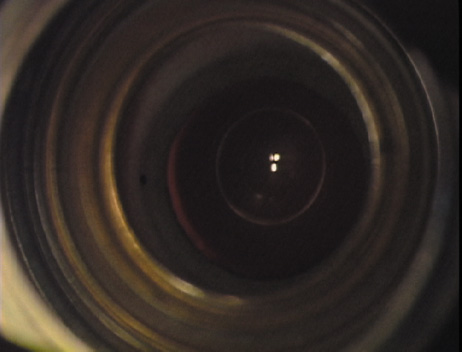

Case 3 is a 48-year-old bilateral hyperope who presented for a refractive surgical consultation. The refraction in his left eye was found to be +3.25 +1.75 × 85. Keratometry was somewhat flat but confirmed WTR cylinder as did corneal topography. Based upon the patient's age, refraction, and somewhat shallow anterior chambers, the decision was made to proceed with a refractive lens exchange. The NAPA nomogram called for LRIs of 55 to 60 degrees with intraoperative pachymetry. Intraoperative keratoscopy confirmed the steep 85-degree meridian (Figs. 2029).

Fig. 20. Keratoscopy, after lifting of the speculum to relieve induced pressure and distortion of the corneal mires, confirms the steep axis of 85 degrees.

Fig. 21. The broad hash marks of the fixation ring are centered just off of the 6:00 limbal orientation mark, over the 85 degree meridian in this left eye. The two cut RK marker is positioned at one extent of the LRI, just under 30 degrees from the central steep meridian and the cornea is marked.

Fig. 22. A second mark is made delineating the opposite extent for a total arc length of just under 60 degrees.

Fig. 23. Following pachymetry measurement over the entire arc length of the incision, an adjustable micrometer diamond knife is set to 90% of the thinnest reading obtained.

Fig. 24. The inferior incision is begun.

Fig. 25. The incision is completed for a total arc length of just under 60 degrees.

Fig. 26. The opposing superior LRI is begun.

Fig. 27. The incision is completed at the corneal mark.

Fig. 28. 6A side-port incision is created for the surgeon's non-dominant right hand, taking care not to intersect the LRI.

Fig. 29. The single-plane RLE incision is completed.